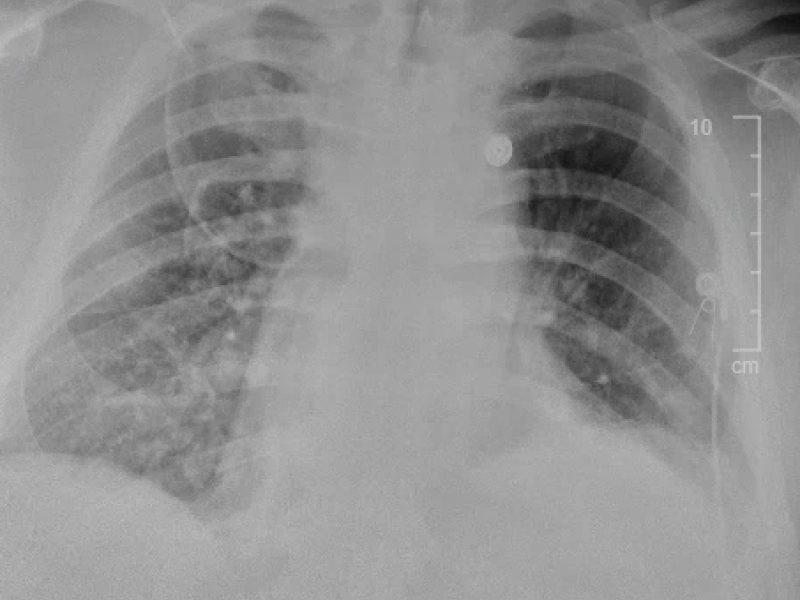

A 30 yo M presents to the ED complaining of atraumatic lower